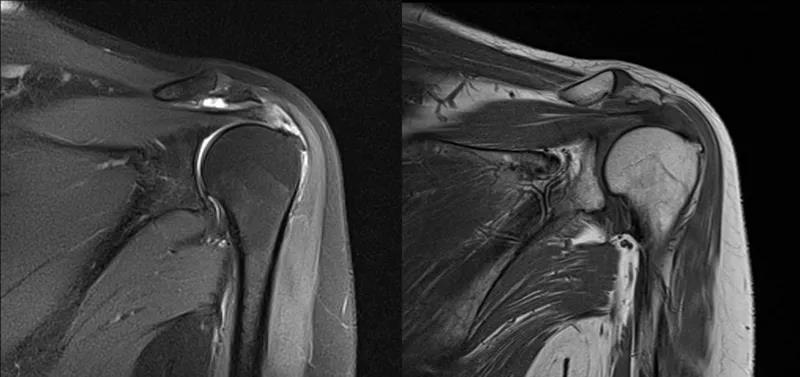

图21 斜冠状位(临床常用)a.T2,b.T1

图22 斜矢状位 a.冈上肌出口,肩袖诊断不如斜冠状位;b.冈上肌及肌腹脂肪浸润成度,评估手术与否

图23 横断位a.正常肩胛下肌;b.肩胛下肌损伤